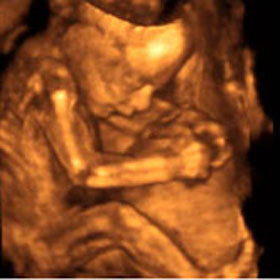

22 неделя беременности

image 26го на узи 3д пойду!!! Тоже вот так свою лялечку хочу разглядеть)))))